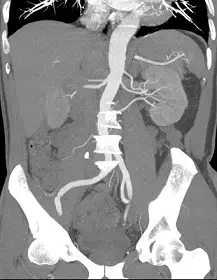

31.電腦斷層檢查如下圖,下列敘述何者最適當?

- 影像切面與技術:這是一張腹部電腦斷層血管攝影(CTA)的冠狀面(Coronal view)最大強度投影(MIP)影像。高密度的部分包含打入對比劑的動脈血管以及骨骼(如腰椎、骨盆)。

- 主要血管構造:畫面正中央垂直向下延伸的粗大血管為腹部主動脈(Abdominal aorta)。

- 兩側分支與器官:在主動脈兩側約 L1-L2 腰椎高度,可明顯看到成對的血管向外側水平延伸,並進入兩側呈蠶豆狀的實質器官。這些蠶豆狀器官為腎臟(Kidneys),而向兩側走行的血管即為腎動脈(Renal arteries)。

- 解剖變異特徵:特別觀察影像右側(即病患的解剖左側),可以發現進入左腎的動脈不只一條,而是有多分支同時進入腎門,這是臨床上常見的**副腎動脈(Accessory renal artery)**解剖變異。評估此類血管變異是臨床安排腎動脈 CTA (如活體